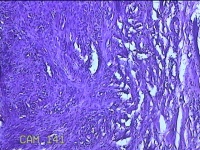

左侧臀部结节

性别

男

年龄

40岁

临床诊断

皮下结节

一般病史

发现左侧臀部结节1年余。

标本名称

大体所见

灰白粉红色组织1.3x0.8x0.3cm一块,表面带梭形皮肤1.3x0.8cm,皮下见结节1.3x1x0.7cm一个,切开结节呈实性,切面灰白粉红色,质软。